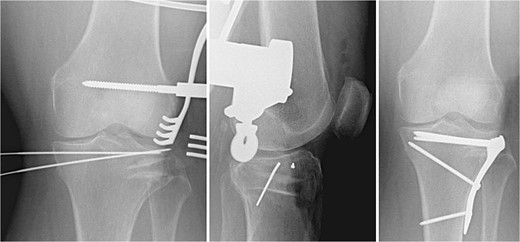

A 3.5 locking compression plate (LCP) proximal tibia plate is selected and centered on the bone to buttress the lateral condyle and the allograft. The plate is temporarily fixed with two K-wires proximally and distally. When satisfied with the plate position, a 2.5 mm drill bit and a universal drill guide are used to drill bicortically into the axilla, just distal to the apex of the fracture. After measurement of the required length with a depth gauge, a 3.5 mm screw is placed. The same process is repeated in a percutaneous fashion to place a distal 3.5 mm screw through a stab incision. Proximal 3.5 mm locking or non-locking screws, based on surgeon preference and bone quality, are filled using the 2.8 or 2.5 mm drill bit, respectively. The K-wires are removed, and final x-rays are obtained. The medial proximal tibial angle and posterior slope are measured and compared to the contralateral extremity (Fig. 3).

Fracture fixation using 3.5 mm LCP proximal tibia plate, rafting screws, and tricortical iliac crest allograft holding the articular surface.